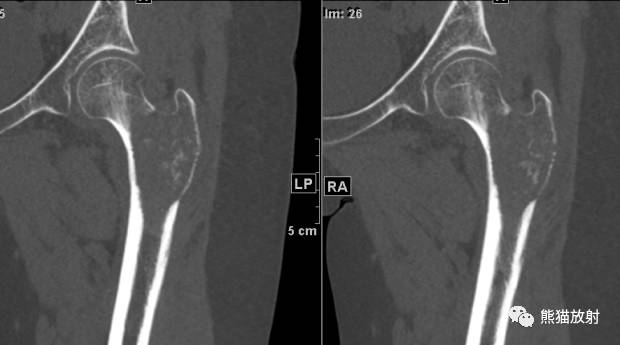

↓ 多发性骨髓瘤

II型 ↓ 肱骨骨髓炎(金葡菌)